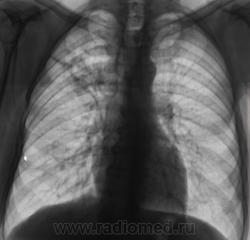

И откуда он берется? Очередной контроль после флюорографии.

Контроль передвижного флюорографа.

Сегодня дообследовали.

да тубркулеза у Вас хватает!

Но может оказаться и пневмонией..

Не оказался "пневмонией". Сегодня пришел коллега фтизиатр записать изображения на диск, посылает пациента в ОПТД, палки найдены.